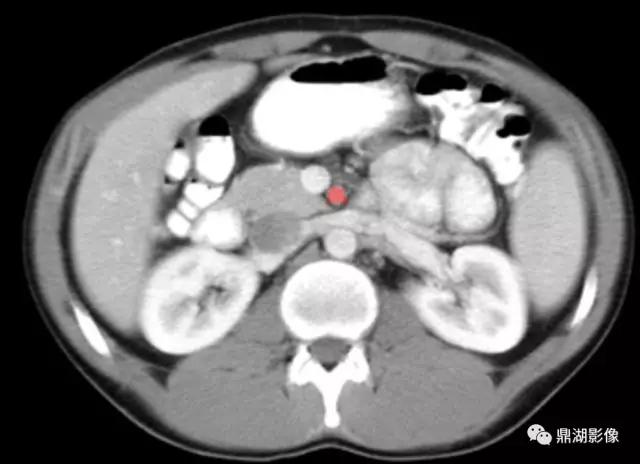

肠系膜上动脉(Superior Mesenteric Artery)

肠系膜上静脉(Superior Mesenteric Vein)